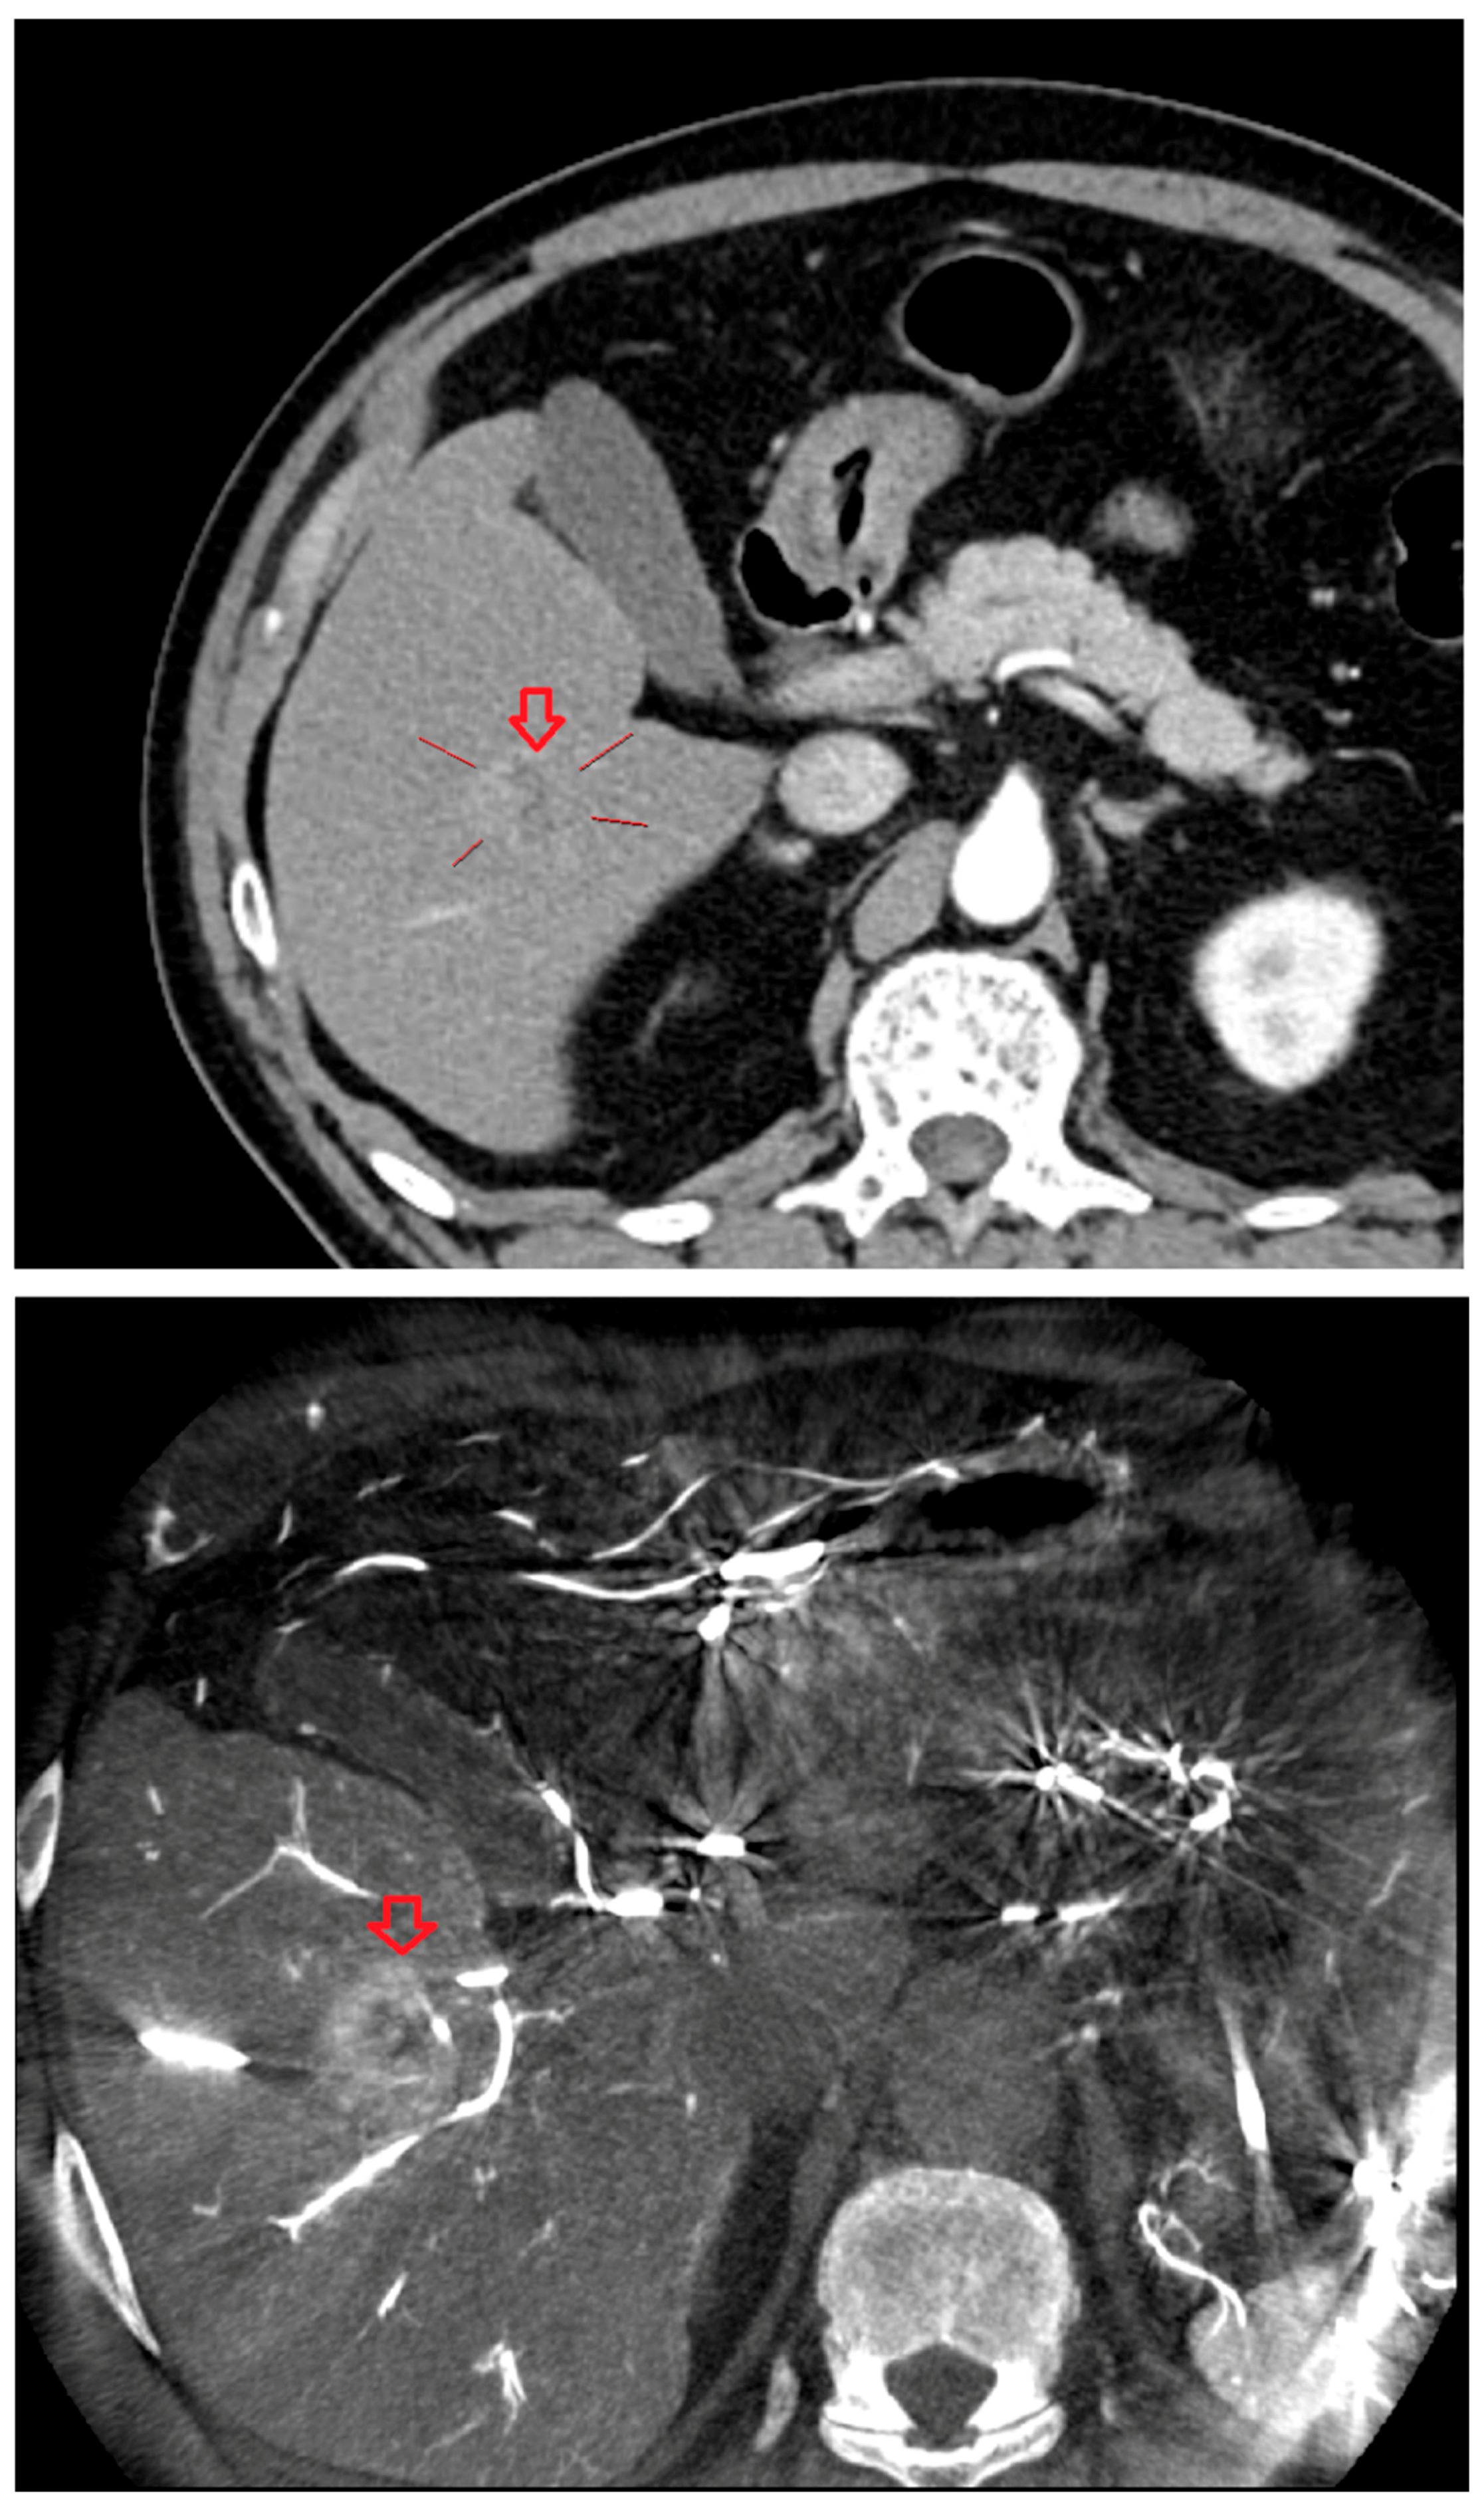

As shown in Figure 1, angio-CBCT allows for higher visibility of the target mass, as reflected in the ΔHU values. This can be visually confirmed in several cases. Representative cases in Figure 2 and Figure 3 demonstrate how the target mass is much more conspicuous to the operator on angio-CBCT compared to pre-procedural CT. In Figure 4, a mass, which was nearly invisible on pre-procedural CT, was identified through angio-CBCT, aiding the targeting process. Figure 5 shows a case where a mass with discordance between USG and CEUS was confirmed using angio-CBCT, leading to needle repositioning and achieving complete ablation. Finally, Figure 6 illustrates a case where a residual tumor was identified on angio-CBCT and re-ablation resulted in complete ablation.

Figure 4. Images from another patient with hepatocellular carcinoma undergoing angio CBCT-guided RFA. All red arrows indicate the HCC mass. (Left): pre-procedural CT (portal phase). (Middle): pre-procedural MRI (arterial phase). (Right): intraprocedural angio CBCT. (Intra lesion − Intra background = 432.7 HU).

Diagnostics 15 02898 g004